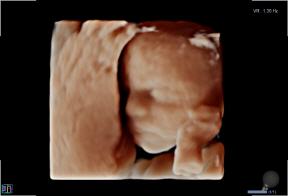

3D/4D-Ultraschall für Schwangere

Seit März 2019 steht ein neues 3D/4D-Ultraschallgerät für faszinierende Eindrücke von Ihrem Baby zur Verfügung.

Außer den Fotos können auch 3D/4D Viedeoclips gemacht und auf einem USB-Stick gespeichert werden. So können die Bilder und Clips jederzeit angesehen werden.